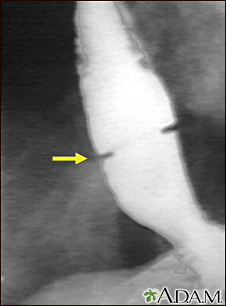

Schatzki ring - x-rayBackSchatzki ring - x-rayA solution containing a dye (barium), which is visible on x-rays, has been swallowed (upper GI series) and x-rays have been taken of the esophagus. There is a narrowing near the stomach (indicated by the arrow). This non-cancerous ring of tissue (Shatzki ring) may cause swallowing problems (dysphagia) and can be treated with dilation of the stricture. E-mail FormEmail ResultsName:Email address:Recipients Name:Recipients address:Message: